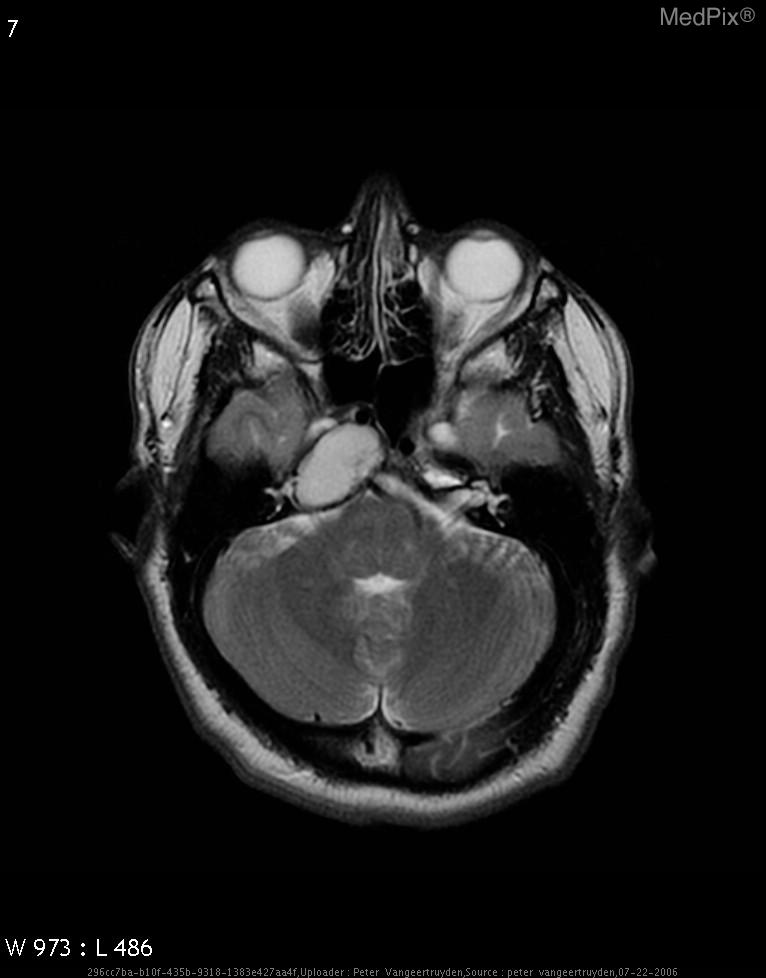

Cholesterol granuloma

• Diagnosis: Cholesterol granuloma

- Axial MRI brain shows a large, well-defined, expansile lesion centered in the petrous apex region on the image-left (patient-right).

- Lesion demonstrates homogeneously high signal intensity on T2-weighted sequence, suggesting fluid or blood product content.

- The mass appears to cause remodeling and expansion of the petrous temporal bone on the image-left (patient-right).

- No definite internal septations or solid enhancing nodules are visible on this T2 image.

- Adjacent structures such as the cerebellum and pons are mildly compressed but not invaded.

- The middle ear and mastoid on the image-left (patient-right) appear partially effaced.

- Optic apparatus and contralateral (image-right, patient-left) structures are normal.

- No diffusion restriction or perilesional edema is observed on this sequence (though confirmation requires DWI).

2) Most likely diagnosis and why:

Cholesterol granuloma of the petrous apex (image-left = patient-right). This diagnosis is favored due to the well-circumscribed expansile lesion in the petrous apex with homogeneous T2 hyperintensity and smooth bony expansion, typical for a cholesterol granuloma containing blood degradation products. No solid component or irregular enhancement pattern suggests a cystic, benign process rather than neoplastic. Context consistency: Consistent — matches the provided context of petrous apex cholesterol granuloma in a 64-year-old female. Confidence: 90%